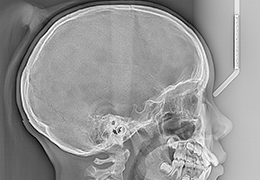

ANYTHINK 经导管主动脉瓣膜置换术分析系统